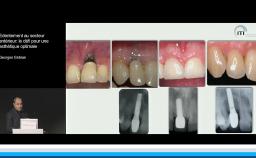

Evaluation du risque esthétique en implantologie orale maxillaire antérieure unitaire

Didier Eycken

La présentation s’attache à détailler en quoi l’implantation en zone esthétique constitue un challenge lorsqu’il s’agit de réhabiliter la fonction sans oublier de rétablir l’esthétique. A travers quelques cas cliniques, le Dr Eycken s’appuie sur la classification SAC de l’ITI pour évaluer la complexité du cas et y apporter la solution thérapeutique adaptée. Il revient également sur l’importance du positionnement de l’implant dans les 3 sens de l’espace et sur la qualité des tissus mous environnants.